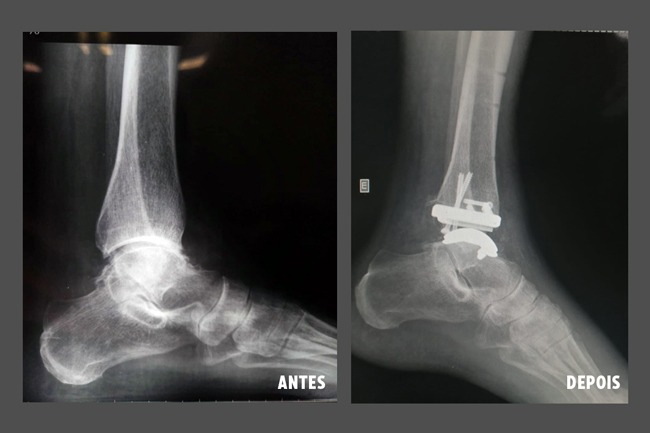

A Unimed Jundiaí, na última sexta-feira (8) por meio do ortopedista e médico cooperado Dr. Raul Munch Cavalcanti, realizou a primeira cirurgia de artroplastia total de tornozelo, ou seja, implante de prótese de tornozelo, com supervisão do Dr. Guilherme Honda Saito, referência no procedimento no país.

O paciente, um senhor de 75 anos de idade, apresentava um caso específico de osteoartrose, um degaste da cartilagem deste membro que gera atrito entre as superfícies ósseas, fazendo com que o paciente sinta dor e dificuldade para apoiar o pé no solo.

“A artroplastia de tornozelo é indicada para casos de osteoartrose dessa articulação, substituindo a articulação do tornozelo por uma prótese metálica visando manter a mobilidade e o alívio da dor, melhorando assim a qualidade de vida do paciente. Não são todos os casos de artrose que podem se beneficiar desse tratamento, há muitos critérios para a indicação”, explica Dr. Raul.